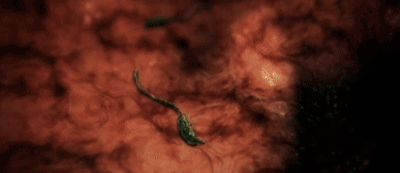

医生在检查后 , 也被他的情况惊呆了 , 因为在Jake的眼睛里 , 他发现了一只猪肉绦虫 。 虽然罕见 , 但其实这种寄生虫有时会从肠道移动 , 方向有两个选择:脑部或者是眼部 。

而Jake当时的情况已经相当糟糕 , 可能连眼球都保不住 。

不过 , 他还算是幸运的 , 手术进行的很顺利 , 经历过痛苦的他 , 又能开车了 。